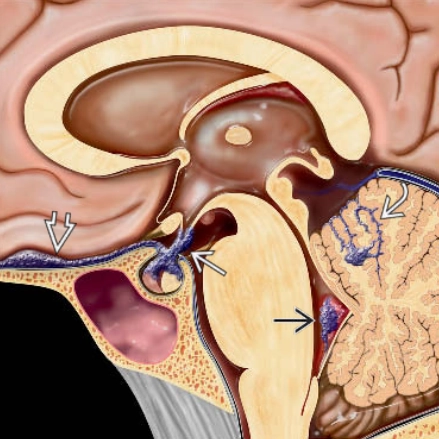

• Thoát vị não (Brain herniation)

• Thoát vị dưới liềm (Subfalcine Herniation - SFH)

• Thoát vị móc hải mã (Uncal Herniation)- Thoát vị xuyên lều xuống dưới một bên (Unilateral Descending Transtentorial Herniation)

• Thoát vị trung tâm (Central Herniation)-Thoát vị xuyên lều xuống dưới hai bên (Bilateral Descending Transtentorial Herniation)

• Thoát vị lều tiểu não hướng lên (Ascending Transtentorial Herniation)

• Thoát vị hạnh nhân tiểu não (Tonsillar Herniation)